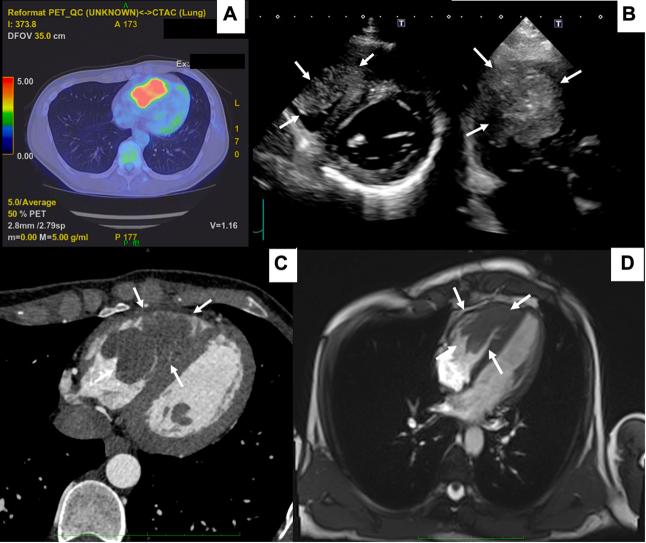

经手术切除治疗的尤因肉瘤右心室转移

Right Ventricular Metastasis of Ewing Sarcoma Treated Through Surgical Resection.

A 27-year-old man diagnosed with right ventricular metastasis of Ewing sarcoma was referred to our institution. We surgically resected the metastatic tumor to prevent sudden death and reconstructed the right ventricle and tricuspid valve. He has survived for 1 year postoperatively without recurrence.

摘要

一名27岁被诊断为尤因肉瘤右心室转移的男性患者被转诊至我院。我们通过手术切除转移瘤以预防猝死,并对右心室和三尖瓣进行了重建。他术后已存活1年,无复发。